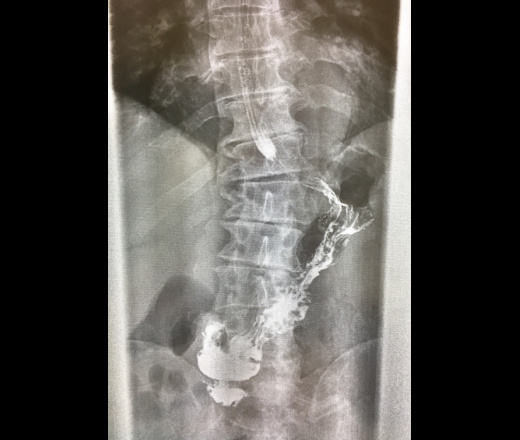

Был на исследовании мужчина, жалоб не предьявляет , кроме низкого гемоглобина - 88г/л.Пациент после ФГДС, в заключении которого: лейомиома 12пк. Можно вообще мнение?

По передней стенки верхнего отдела в описании. Лейомиома под?не уверена что хорошо провела исследование, не достаточно вывела 12 пк( подскажите как быть.  Может через месяц пригласить пациента?

Ни на одном снимке дефекта наполнения не нашла. Не имею морального права писать "леомиома". Снимков маловато будет. Если исследование целенаправлено, надо или подтвердить, или опревергнуть искомое всеми доступными приемами (снимки зоны интереса прицельно, полипозиционно, с компрессией, двойным контрастированием)